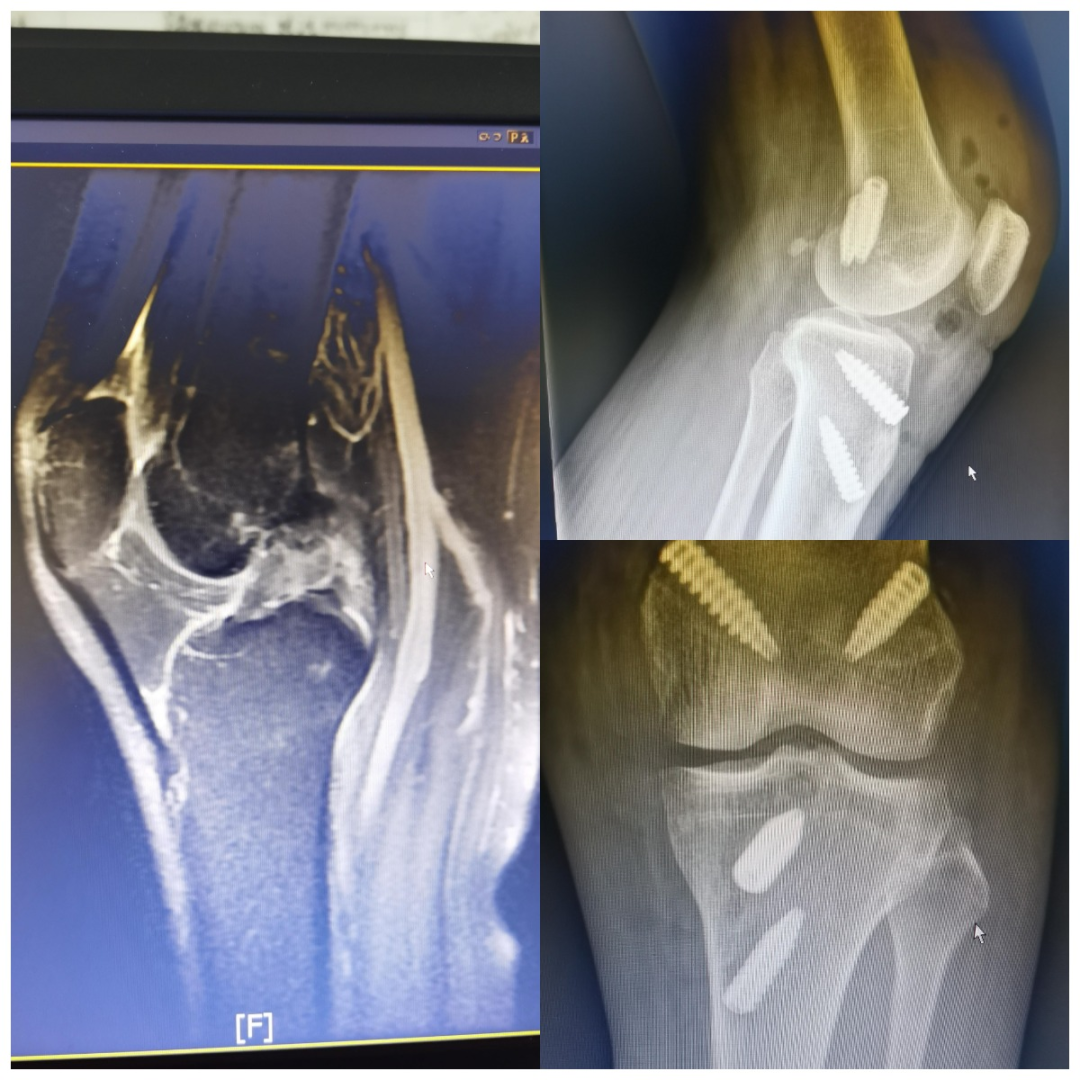

在骨科陈子华主任、曾红生副主任医师及关节运动医学团队结合患者入院后膝关节MRI及术前MRI,左膝前后交叉韧带断裂诊断明确,考虑到患者术前已制动1月余,手术后不适合长时间限制运动,最终选择人工韧带(LARS)重建前后交叉韧带。采用关节镜微创手术,术中透视见挤压钉固定位置准备,仅用5个微创小切口就为患者完成了手术,出血约为10ml。术后第一天患者就可使用CPM机进行功能康复训练,术后5天患者可屈膝到90°,1周扶拐杖行走,2周非负重行走,顺利出院。

术前及术后复查拍片